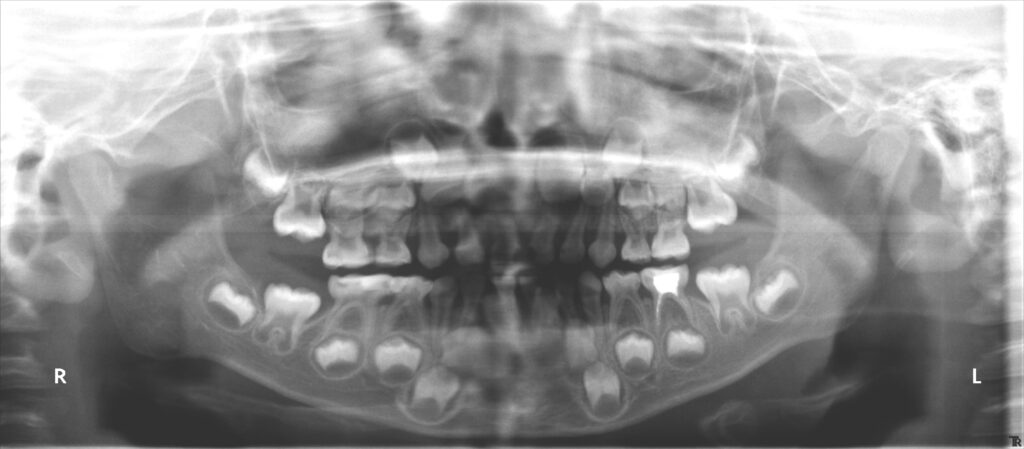

治療前

- 初診:2014年、8歳男児、

- 診断:1級咬合、左偏位、下永久歯(犬歯)萌出スペース不足

- 治療方針:非抜歯で行う。虫歯予防(フッ素)、歯磨き指導、舌位の改善、上下拡大床+補助断線→マウスピース矯正→下親知らずの抜歯、保定→メンテナンス

13歳頃、永久歯列になったところで、1期治療終了。後は親御さんが希望されたため、メンテナンスに移行し、高校生になったら下の親知らずを抜歯することにしました。

高校2年生で下の左右の埋伏の親知らずを抜歯しました。下の埋伏親知らずは、将来の歯並びの予後に悪い影響を与えたり、年齢が上がるにつれて抜きにくくなるので、できれば早期の抜歯が望ましいと考えています。一方、上の親知らずのは抜歯は簡単なことが多く、手前の7番や開咬などの不正咬合に悪い影響をあたえなければ、下程急ぐ必要はないかもしれません。当医院では一応下の親知らずの抜歯をもって、ある程度の矯正は終了と捉えています。しかし、管理されるのが嫌、抜きたくない方、他(高次機関等)で抜歯したいという方は13歳位で1期治療は終了という方針です。